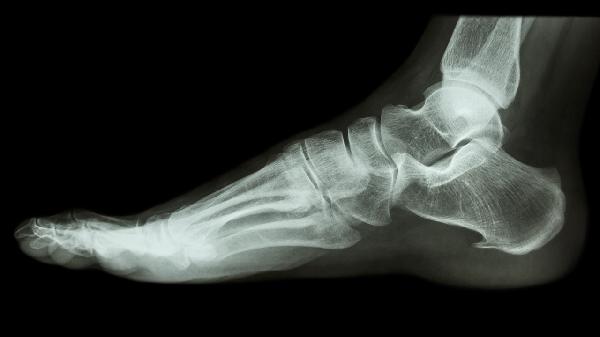

通过X线或CT检查可见骨折线周围出现云雾状钙化影,表明成骨细胞开始修复。骨痂通常先出现在骨折端压力侧,4-6周后逐渐桥接骨折线。若配合补充维生素D钙剂和蛋白质摄入,可促进骨痂成熟。延迟愈合者可能需要脉冲电磁场或体外冲击波干预。